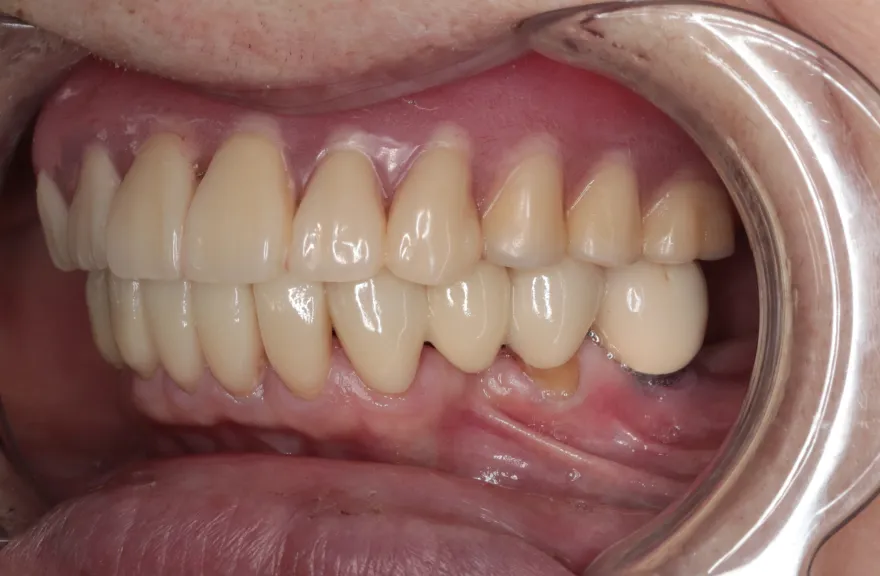

上顎は5本の歯を保険のブリッジ治療で連結してある状態でした。どの歯の状態も良くなく、今回なんとか治療を行ったとしても近いうちに再びトラブルを起こしてくることが予想されました。

下顎は9本の歯が残っており、虫歯はあるものの差し歯として使える状況でした。

しかし、患者さんとの話し合いの中で、「数年前に行った治療なのに再び全てやりかえないといけないのは単純にしんどい。もうやりかえのないようにしたい」という患者さんの強い思いが伝わってきました。

今回で完全に治療をやり切ってしまい、今後は最小限の介入で歯科と付き合えるよう、上下顎残っている歯の全ての抜歯、必要な本数のインプラント埋入、上顎は総義歯形態で対応することとしました。 - 治療のリスク